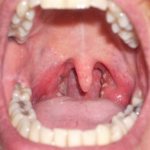

Как выглядит молочница на губах у ребенка?

Сам родитель может узнать начало недуга по характерному внешнему виду. Фото молочницы на губах у ребенка поможет домашним распознать “врага» еще до посещения педиатра.

Это не составит большого труда, так как отличительный признак молочницы во рту – это появление белого налёта, который может покрывать язык, дёсны, внутреннюю поверхность щёк, нёбо, гланды, миндалины.

Специфический налёт, похожий на манные крупинки (в запущенных случаях он может напоминать частички творожка), является первичным признаком молочницы.

На начальном этапе развития молочница не доставляет малышу особого дискомфорта. Внешне она проявляется небольшими покраснениями на языке, внутренней стороне губ и щек.

Через несколько дней они начинают покрываться белым налетом, который напоминает творог. Чтобы понять, что это именно молочница, следует легко провести чистой салфеткой по языку или губам.

Остатки пищи снимутся, если же это грибковый налет, он останется на месте.

Характерный признак молочницы – белый налет, напоминающий жидкий творог или прокисшее молоко, на поверхности губ. Как правило, впервые он появляется на нижней губке, которая отекает и краснеет. Далее происходит распространение процесса на слизистые внутри – десна, щеки, небо.